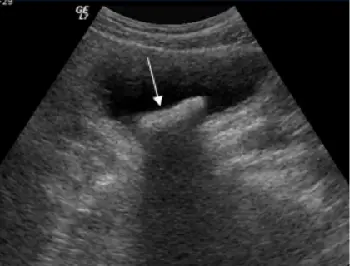

附圖為下腹部超音波掃描,影像中箭號所指為何?

本影像為下腹部灰階超音波掃描(B-mode ultrasound),可見一個無回音(anechoic)的腔室,即充滿尿液的膀胱(urinary bladder)。

- 影像中央偏後方可見一個強回音(hyperechoic)焦點,反射亮度明顯高於周圍軟組織

- 該強回音結構後方有典型的後方聲影(posterior acoustic shadow),呈現黑色帶狀區域,代表超音波無法穿透此結構

- 結構輪廓較清晰,位於膀胱腔內(而非附著於膀胱壁)

影像解讀: 上述強回音合併後方聲影,加上位於膀胱腔內(且可隨體位改變移動),為膀胱結石的典型超音波三聯徵:強回音 + 後方聲影 + 可移動性。此三項特徵足以與血塊(無聲影)、腫瘤(固著於膀胱壁、有血流訊號)及導管(圓形無回音球囊)區別。